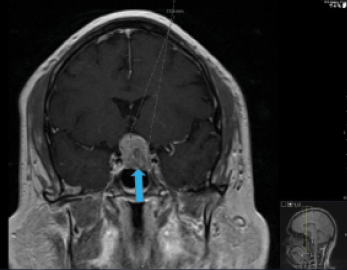

I thought that the changes in this patient’s visual acuity could be attributed to bilateral cataracts. The inferior nasal step in his left eye appeared to be localized to the RNFL. The other visual field changes respected the horizontal meridian, however, and seemed out of proportion to the RNFL damage. I ordered an MRI of the brain with and without contrast and subsequently referred this patient to neurosurgery for treatment based on findings of a pituitary mass (Figures 3–5). He subsequently underwent resection of the mass (Figure 6).

Figure 3. T1-weighted MRI scan, coronal section, with contrast. Blue arrow indicates the growing pituitary mass.

Figure 4. T1-weighted MRI scan, coronal section, with contrast. Blue arrow indicates the growing pituitary mass. Labeled elongated blue arrow indicates the optic chiasm.